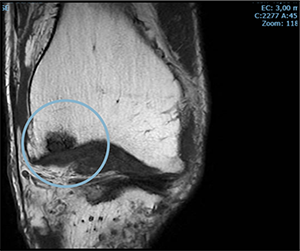

PRE-TREATMENT

AUGUST 13, 2023

POST-TREATMENT

MAY 5, 2024